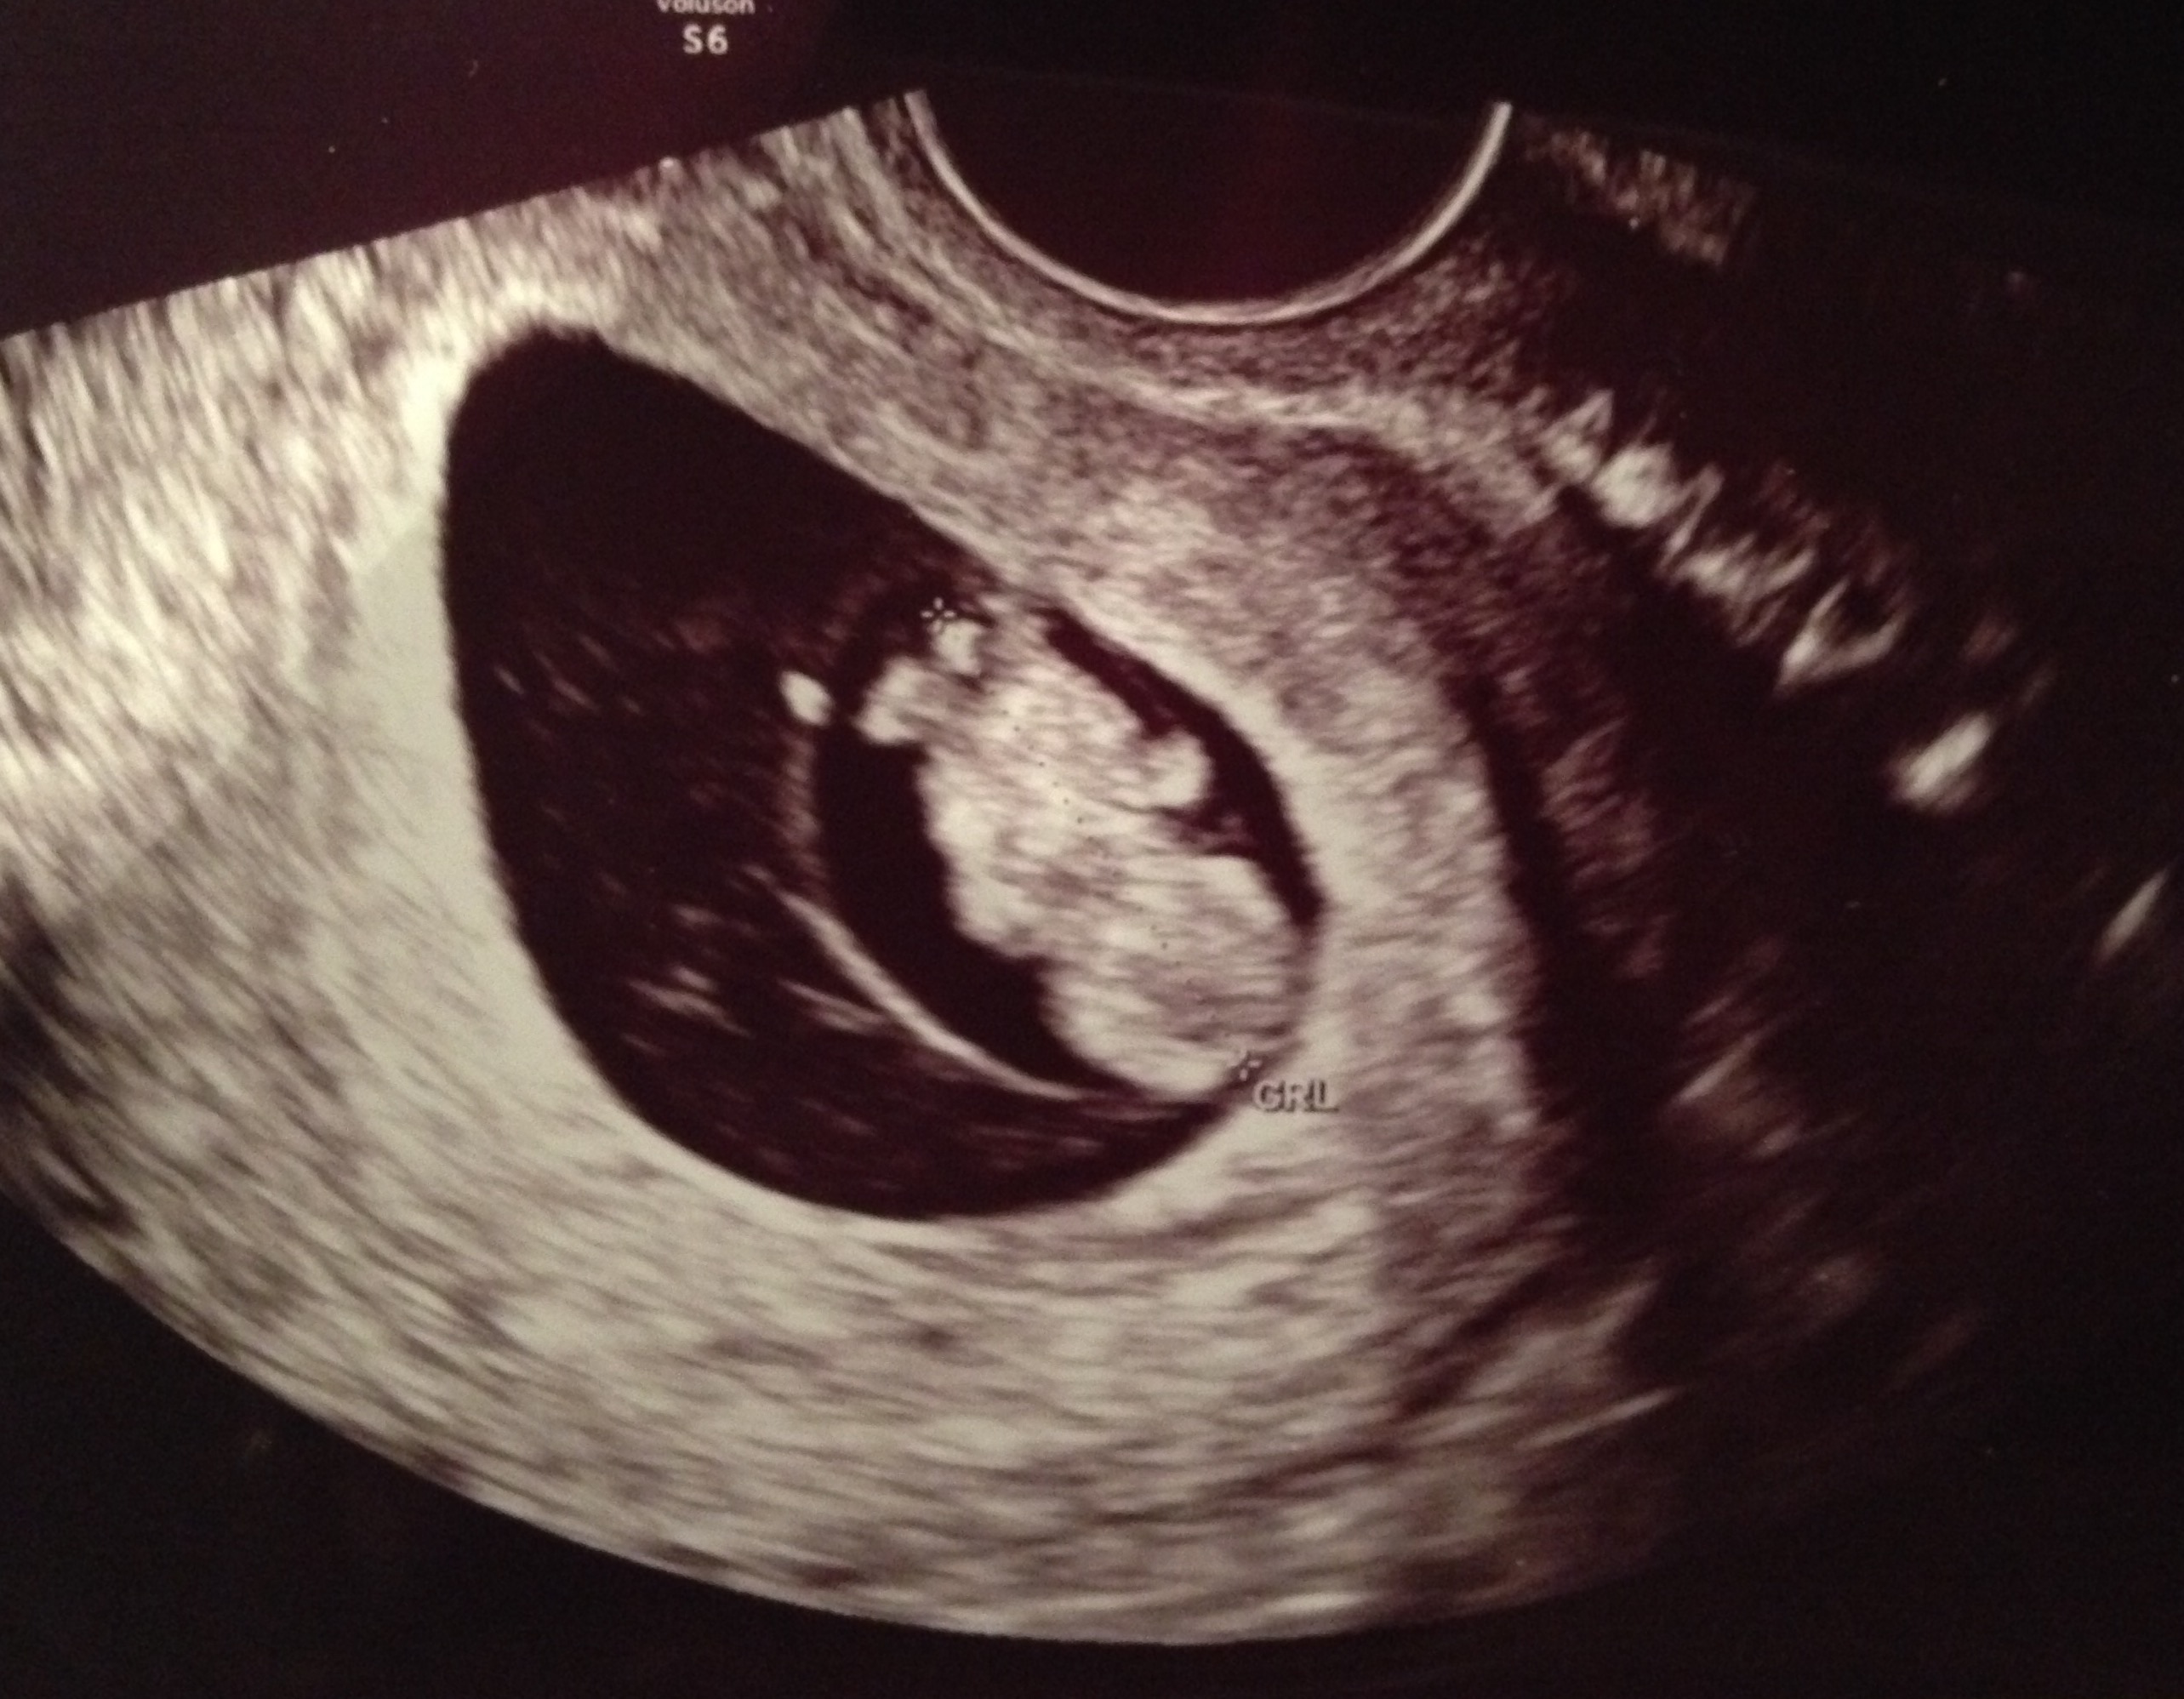

FTM! So excited to see how much my little gummy bear has grown in two weeks! 1st pic is at 6w5d, HR 147, and just a little blob with a flickering heart. 2nd & 3rd pics are at 8w5d, HR 176, and looked so much like a tiny baby with bitty arms and legs. Doc says baby is healthy and quite a dancer, it was moving and waiving all over the place. What a blessed moment to see!